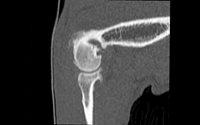

Axial Cuts - Lumbosacral Scanner of a dog - Sagital Reformatting. From the patient's native axial cuts, reconstruction software allows reformatting in all other planes (sagittal, coronal, or oblique). Finally, three-dimensional reconstructions can also be carried out with volume, surface, or endoscopic rendering.

The areas most commonly explored by CT scans in animals are the skull, spine, thorax, abdomen and certain joints such as the elbow or shoulder.

- Exploration of arthropathies of the shoulder: Tenosynovitis, Osteochondritis, Instabilities and lesion of the glenoid bead (arthroscanner)